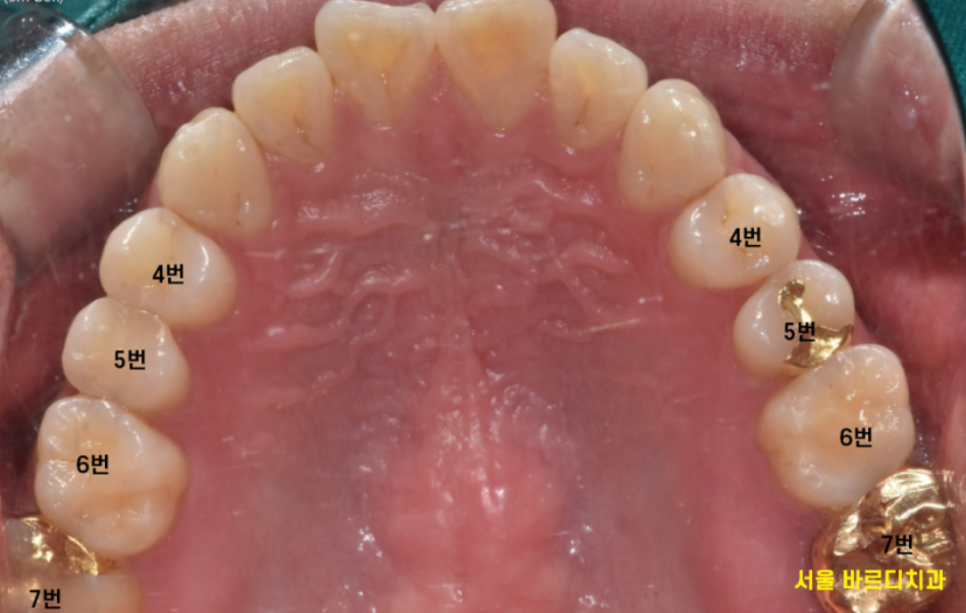

치과 치료 순서에 있어서도 앞니보다 어금니를 먼저 치료하는 것이

씹는 기능이 중요하기 때문입니다.

보여지는 것에 집중하기 보다

환자분의 기능 회복에 초점을 맞춰져 있는지 확인해보세요.